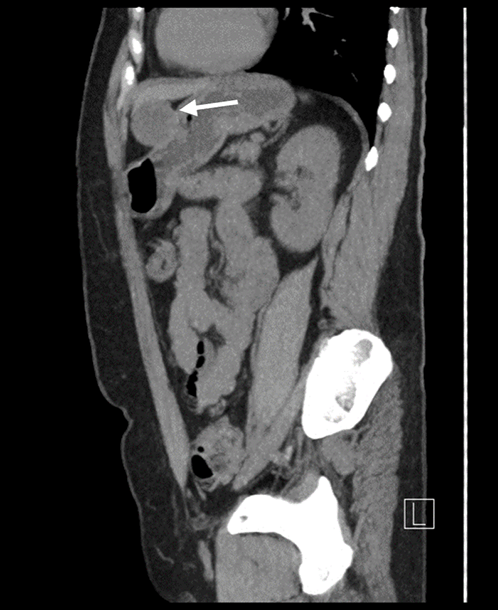

A 62-year-old female with a history of gastroesophageal reflux disease and a 50+ pack year smoking history underwent surveillance chest CT for pulmonary nodules when an incidentally discovered gastric mass was noted. This finding was confirmed with dedicated abdominal and pelvic CT, which demonstrated a 4.1 × 4.3 cm partially exophytic mass on the lesser curvature of the stomach, roughly 9 cm from the gastroesophageal junction (Figure 1). The mass was well circumscribed with no invasion into adjacent structures. Based on the location of the mass and its homogenous appearance on imaging, our initial diagnosis was that of a gastrointestinal stromal tumor (GIST). Apart from the patient’s long-standing reflux disease, she denied any other gastric symptoms.

Figure 1. Dedicated CT Scan of Abdomen and Pelvis After Incidental Discovery of Gastric Mass. Published With Permission